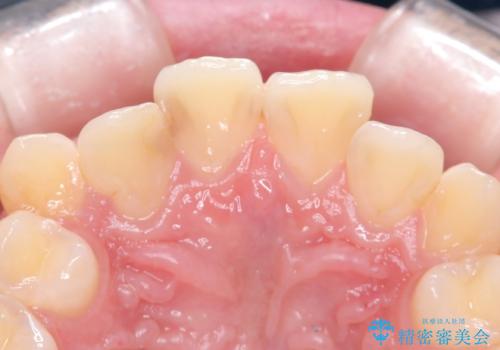

- 主訴:右上の前歯が何しなくても痛い

右上2番の歯に自発痛を認め、症状や歯髄診・レントゲン像から不可逆性歯髄炎と診断し、精密根管治療から歯冠補綴まで行うこととなりました。

初診時に歯髄診断を行い、不可逆性歯髄炎と診断し抜髄から補綴修復までの流れを説明し、精密根管治療、ファイバ-コア築造、オールセラミッククラウン(St)修復を行うこととしました。